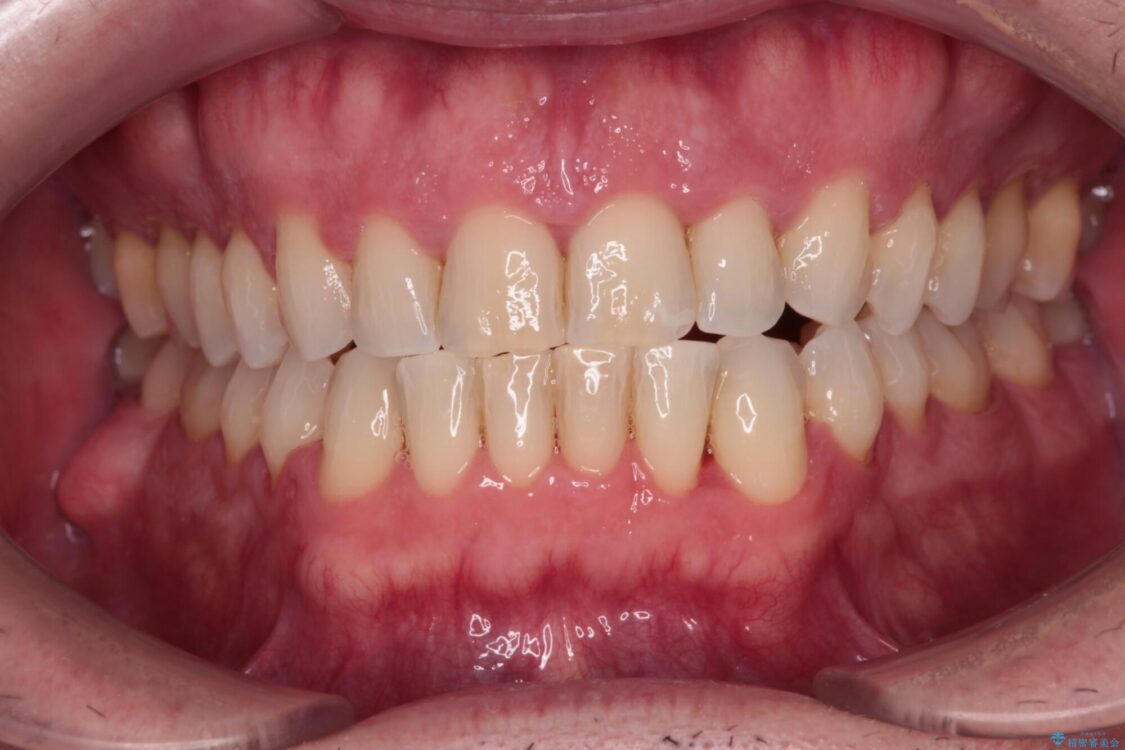

治療後について

舌のトレーニング自体は簡単なものですが、無意識下でも舌が突出しないようにしなければならないため、毎日継続することが最大の難関です。

時間はかかりましたがトレーニングを頑張ってくださり、無事に前歯を接触させることができました。

治療後

• 前歯でものを噛みきりたい 目立たない装置でのワイヤー矯正 治療後画像